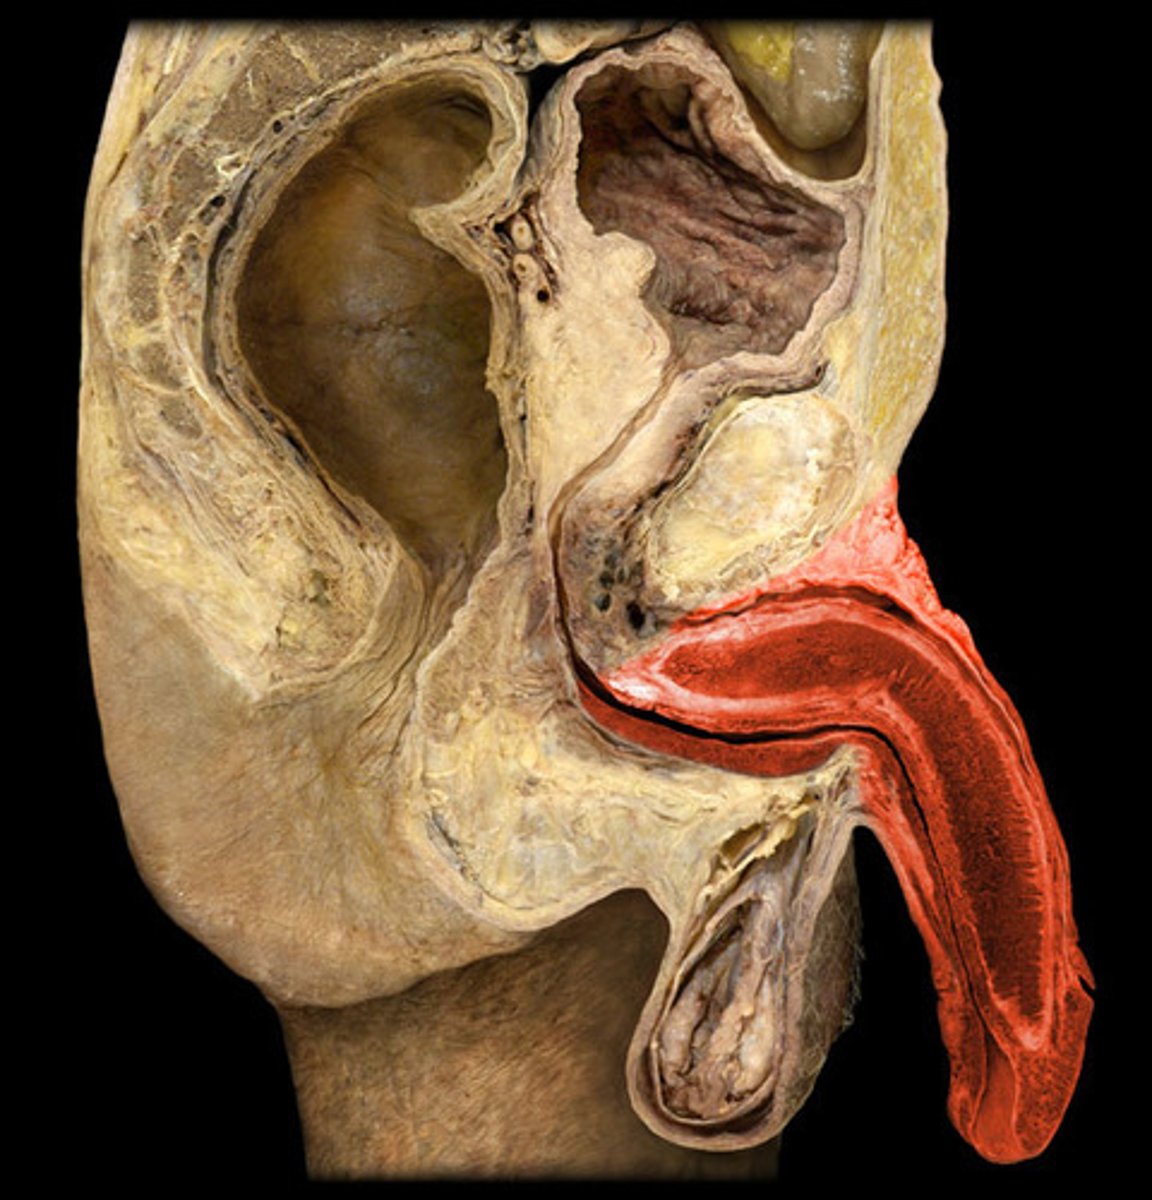

Testis

Epididymis

Spermatic Cord

Vas Deferens

Seminal Vesicle

Prostate

Penis

Corpus Cavernosum

Glans Penis